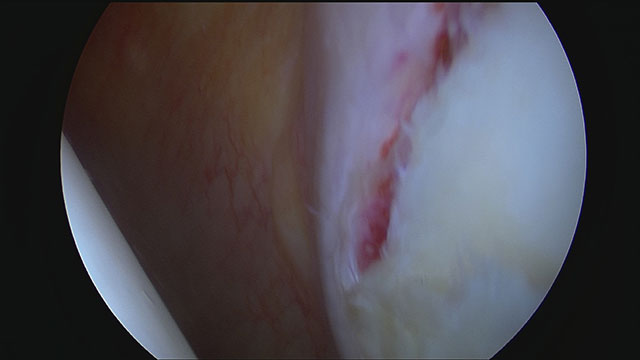

Blick von hinten in die linke Schulter eines Patienten nach Schulterluxation. Im Vordergrund rechts ist die Pfanne. Das Labrum ist abgelöst und die Rissstelle eingeblutet.

Die arthroskopische Bankart-Reparatur gilt als Standardverfahren zur Behandlung von Labrumverletzungen. Hierbei wird das abgerissene Labrum mit speziellen Ankern am Glenoid befestigt. Diese Technik wird besonders häufig bei jungen, aktiven Patienten eingesetzt, die nach einer Erstluxation eine anteriore Instabilität entwickelt haben.

Arthroskopische Bankart-Reparatur